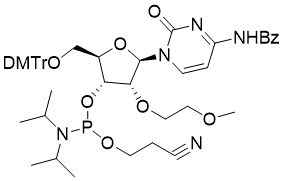

馬鞍山致研生物醫(yī)藥科技有限公司成立于馬鞍山市鄭浦港新區(qū)現(xiàn)代產(chǎn)業(yè)園。公司專(zhuān)注于生物小分子、醫(yī)藥中間體相關(guān)產(chǎn)品的研發(fā)和生產(chǎn),產(chǎn)品主要包括DNA亞磷酰胺單體、RNA亞磷酰胺單體、特殊單體以及按照客戶(hù)要求定制的RNA和DNA,并且公司提供定制合成等方面的研究服...

馬鞍山致研生物醫(yī)藥科技有限公司成立于馬鞍山市鄭浦港新區(qū)現(xiàn)代產(chǎn)業(yè)園。公司專(zhuān)注于生物小分子、醫(yī)藥中間體相關(guān)產(chǎn)品的研發(fā)和生產(chǎn),產(chǎn)品主要包括DNA亞磷酰胺單體、RNA亞磷酰胺單體、特殊單體以及按照客戶(hù)要求定制的RNA和DNA,并且公司提供定制合成等方面的研究服...